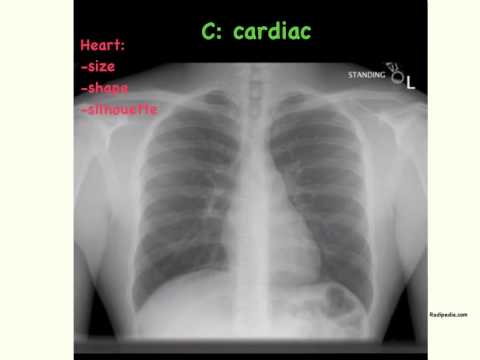

11. Chest X-Ray Reading Method - ABCDE [UndergroundMed] :

how to read chest x ray

12. How to Interpret a Chest X-Ray (Lesson 2 - A Systematic Method and Anatomy) :